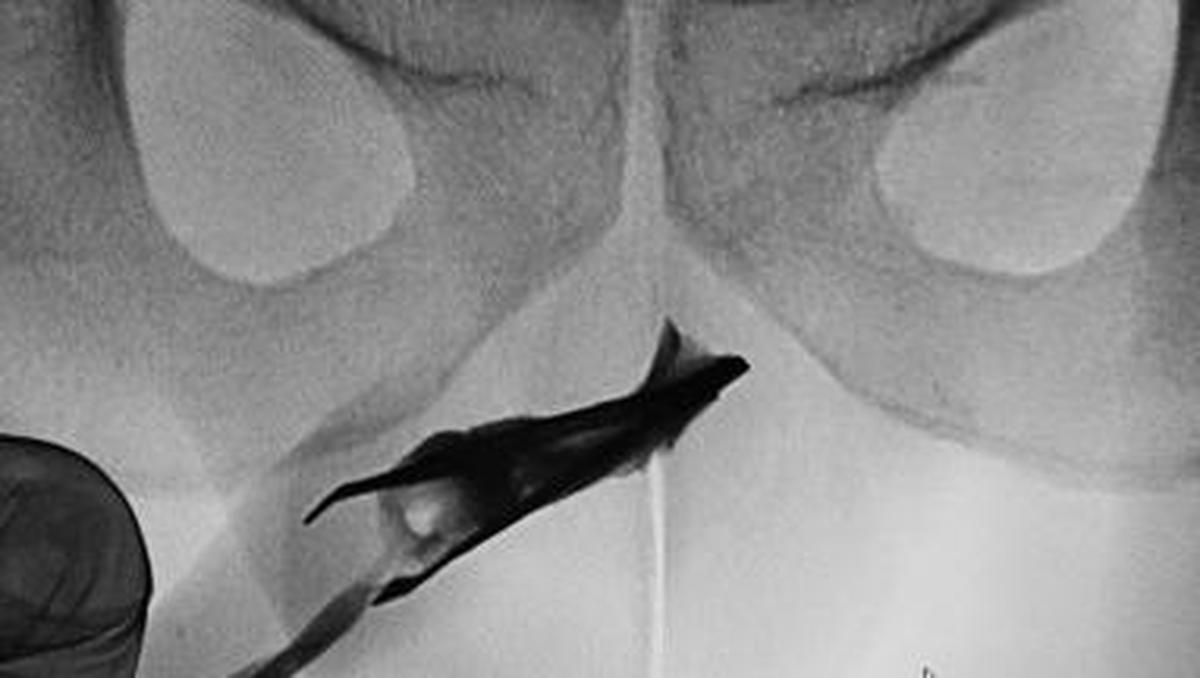

Jakarta – Seorang pasien pria berusia 22 tahun Hingga Arab Saudi datang Hingga Praktisi Medis Di pinset yang menyangkut Hingga penisnya. Benda itu ternyata sudah ada Pada 4 tahun.